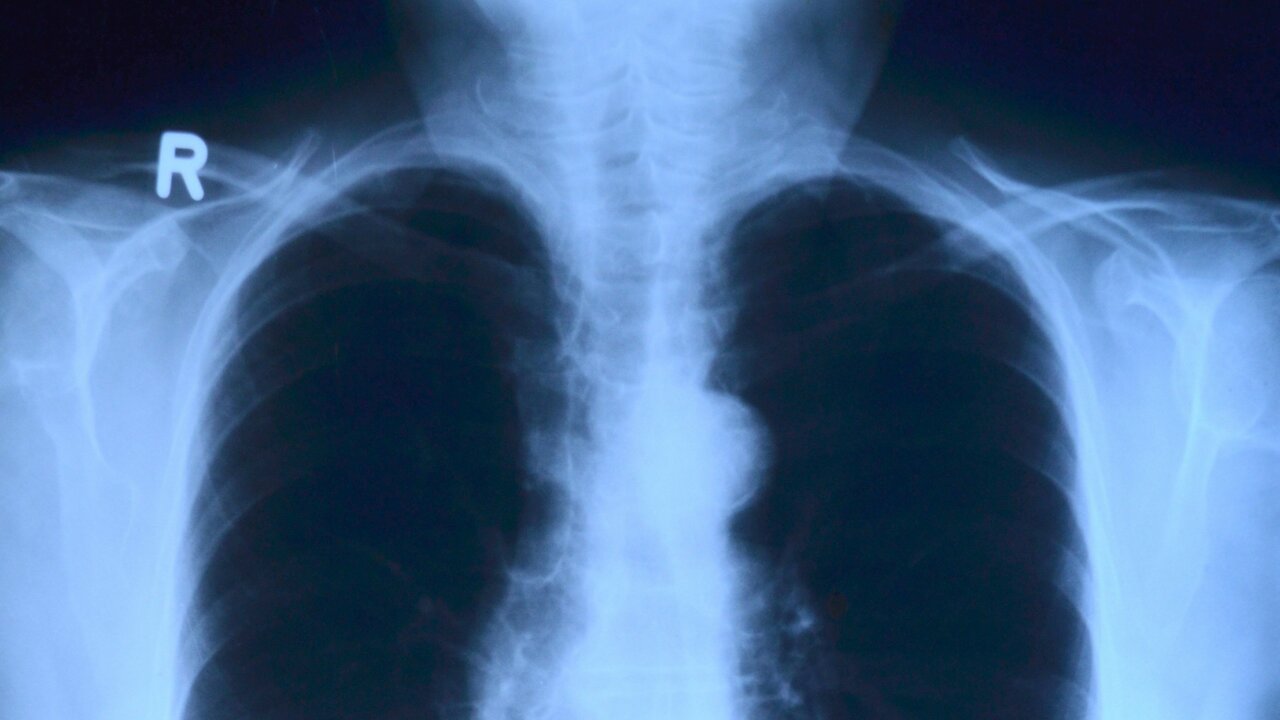

Фото с сайта pixabay.com

Житель США греческого происхождения Стаматис Мораитис прожил около 40 лет после того, как врачи диагностировали у него неизлечимый рак легких и дали не более шести месяцев жизни. Об этом 16 января сообщила газета The Daily Express.

Диагноз был поставлен, когда мужчине было около 60 лет. Несколько американских специалистов подтвердили, что опухоли не поддаются лечению. После этого Мораитис отказался от агрессивной терапии и решил вернуться на греческий остров Икария — место своего рождения, известное высоким уровнем долголетия населения.